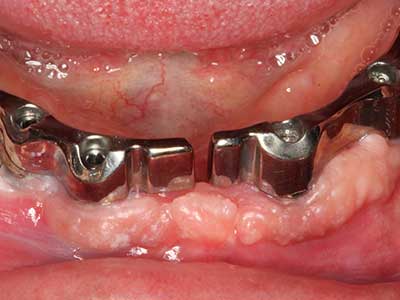

Quando le procedure chirurgiche vengono eseguite sull'osso nelle immediate vicinanze di strutture sensibili, come vasi sanguigni o nervi, gli strumenti rotanti pongono un rischio significativo di lesione iatrogena. I dispositivi piezoelettrici possono essere utili per la preparazione delle coperture ossee e la rimozione del tessuto duro in prossimità dei nervi, in particolare per la loro esposizione dopo una lesione iatrogena, ma anche durante la lateralizzazione dei nervi per le procedure di resezione e ricostruzione o il posizionamento di impianti (figg. 17-20). Il contatto leggero tra puntina piezoelettrica e nervo non causa generalmente danni, ma se si procede senza prestare attenzione con movimenti a sega o raccordi con residui di substrati ossei possono verificarsi danni al nervo temporanei o anche permanenti. Il rischio di danno, tuttavia, è considerato sostanzialmente inferiore al rischio presente utilizzando seghe o frese (Pereira, Gealh et al. 2014).